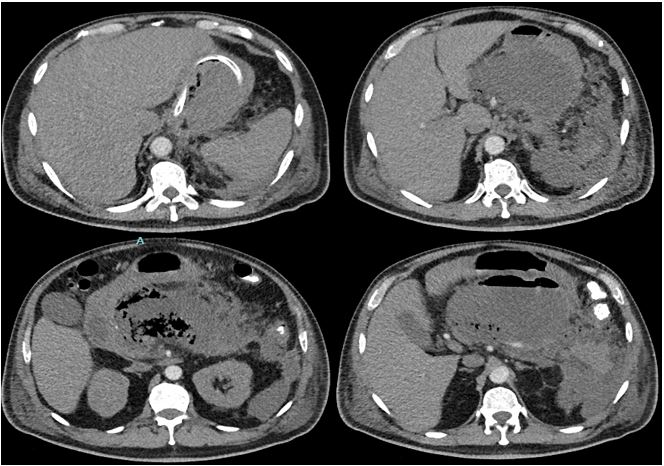

Se presenta el caso de un paciente masculino de 58 años con antecedente de alcoholismo, que consulta en diciembre de 2021 por dolor abdominal generalizado, distensión abdominal, vómitos y ausencia de deposiciones tras ingesta abundante de comida grasa y alcohol. En los exámenes de ingreso se encontró hiperbilirrubinemia (bilirrubina total: 2,3 mg/dL, indirecta: 1,89 mg/dL, directa: 0,41 mg/dL), amilasa sérica elevada (1169 U/dL) y PCR aumentada (212 mg/L). Se diagnosticó pancreatitis aguda. Se inició tratamiento con cristaloides y reposo gástrico. A los 3 días de estancia hospitalaria, desarrolló distensión abdominal, edemas y oliguria, y requirió atención en UCI, nutrición parenteral y antibioticoterapia con ampicilina/sulbactam. Se solicitó tomografía abdominal (Fig. 1) que mostró múltiples colecciones, la de mayor tamaño de 86 ×180 ×110 mm en la transcavidad de los epiplones con amplio contacto con cuerpo gástrico y duodeno, múltiples burbujas y nivel hidroaéreo.

Figura 1. TC de abdomen simple y contrastado Ingreso en UCI: colecciones evidentes a nivel de cuerpo gástrico y duodeno, con múltiples burbujas, nivel hidroaéreo; la de mayor tamaño es de 86×180 × 110 mm; otras, localizadas posteriormente a parénquima esplénico, a nivel parrarenal izquierdo, en corredera parietocólica homolateral, y a nivel del mesenterio, con marcada alteración tomodensitompetrica de los planos adyacentes y ganglios locorregionales.